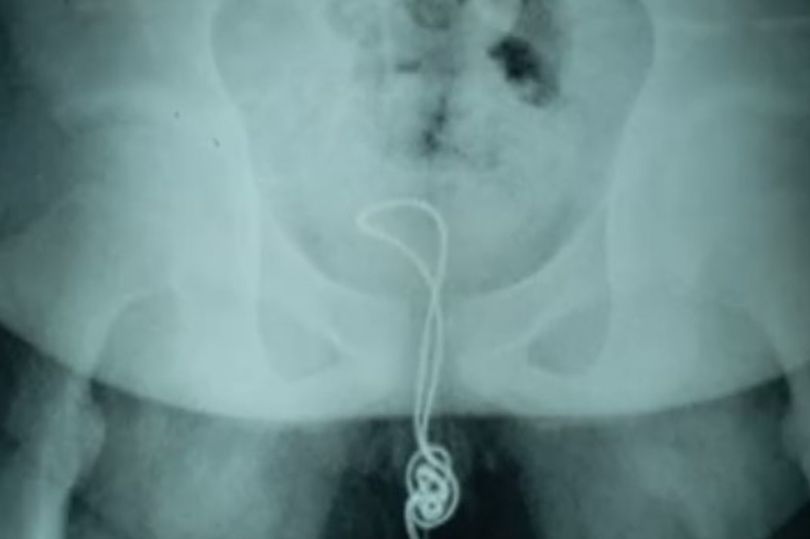

07/07/2018 15:37Dây sạc điện thoại mắc kẹt trong 'của quý' thiếu niên TQ

Nam thiếu niên 13 tuổi được cho là đã nhét chiếc đây sạc điện thoại dài khoảng 20cm vào trong dương vật của mình, trước khi nhận ra cậu không thể kéo sợi dây ra ngoài.

Cậu bé đã được bố mẹ đưa tới bệnh viện địa phương tại huyện Lâm Khẩu thuộc tỉnh Hắc Long Giang, Trung Quốc. Tại đây, các bác sĩ đã sử dụng chất bôi trơn để có gắng kéo sợi dây ra khỏi dương vật của bệnh nhân.

Mặc dù vậy, phương pháp và các bác sĩ áp dụng không thành công và gây đau đớn cho cậu bé. Bệnh nhân sau đó được chuyển tới bệnh viện nhi thành phố Cáp Nhĩ Tân vào ngày hôm sau.

Bác sĩ Xu Liyan, làm việc tại khoa tiết niệu của bệnh viên nhi Cáp Nhĩ Tân, cho biết: “Cậu bé đã cắt một đầu dây sạc điện thoại và nhét nó vào trong đường niệu đạo của mình. Dây cáp đã vào tới bàng quang và bị thắt nút ở đó”.

Bác sĩ Xu và các cộng sự không còn cách lựa chọn nào khác ngoài phẫu thuật cho cậu bé. Họ đã mở bàng quang của bệnh nhân để cắt đoạn dây thắt nút, trước khi kéo nó ra ngoài. Cậu bé xuất viện ngày 3.7, sau 2 tuần điều trị.